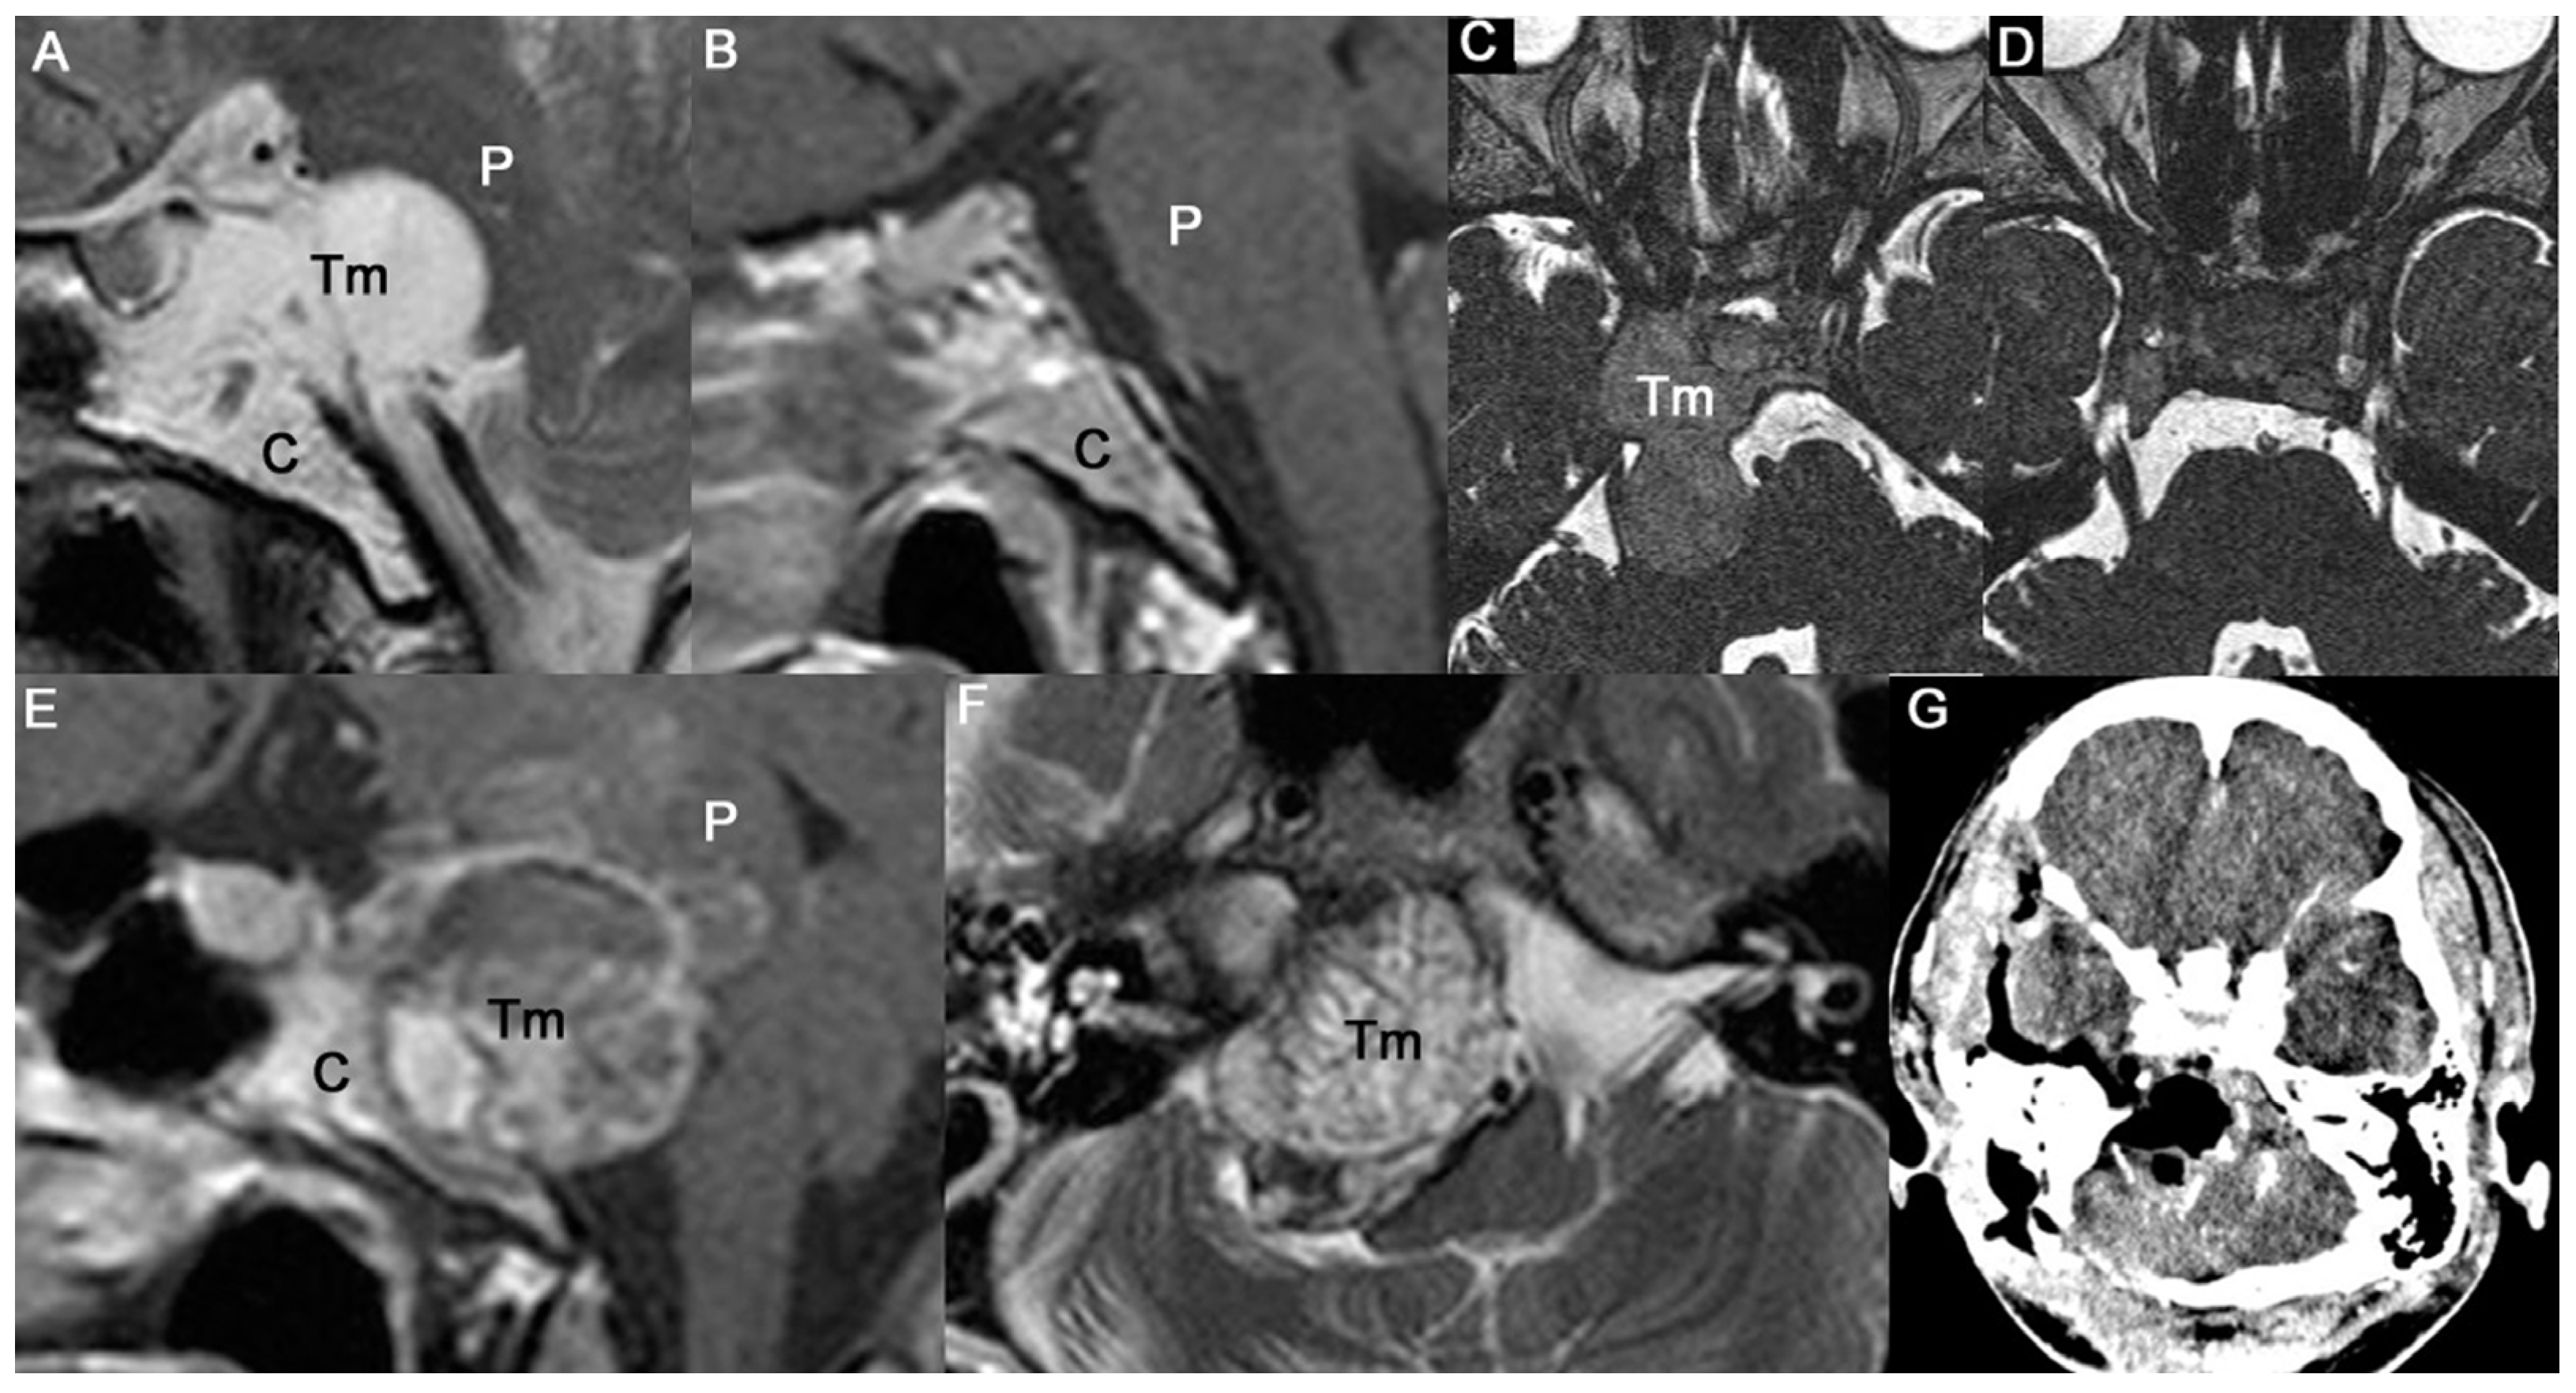

3.1. Tumor Locations and Invasion of Critical Structures

3.2. Overall Outcomes